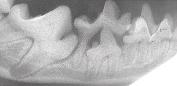

dental x-ray

Notice the impacted tooth.